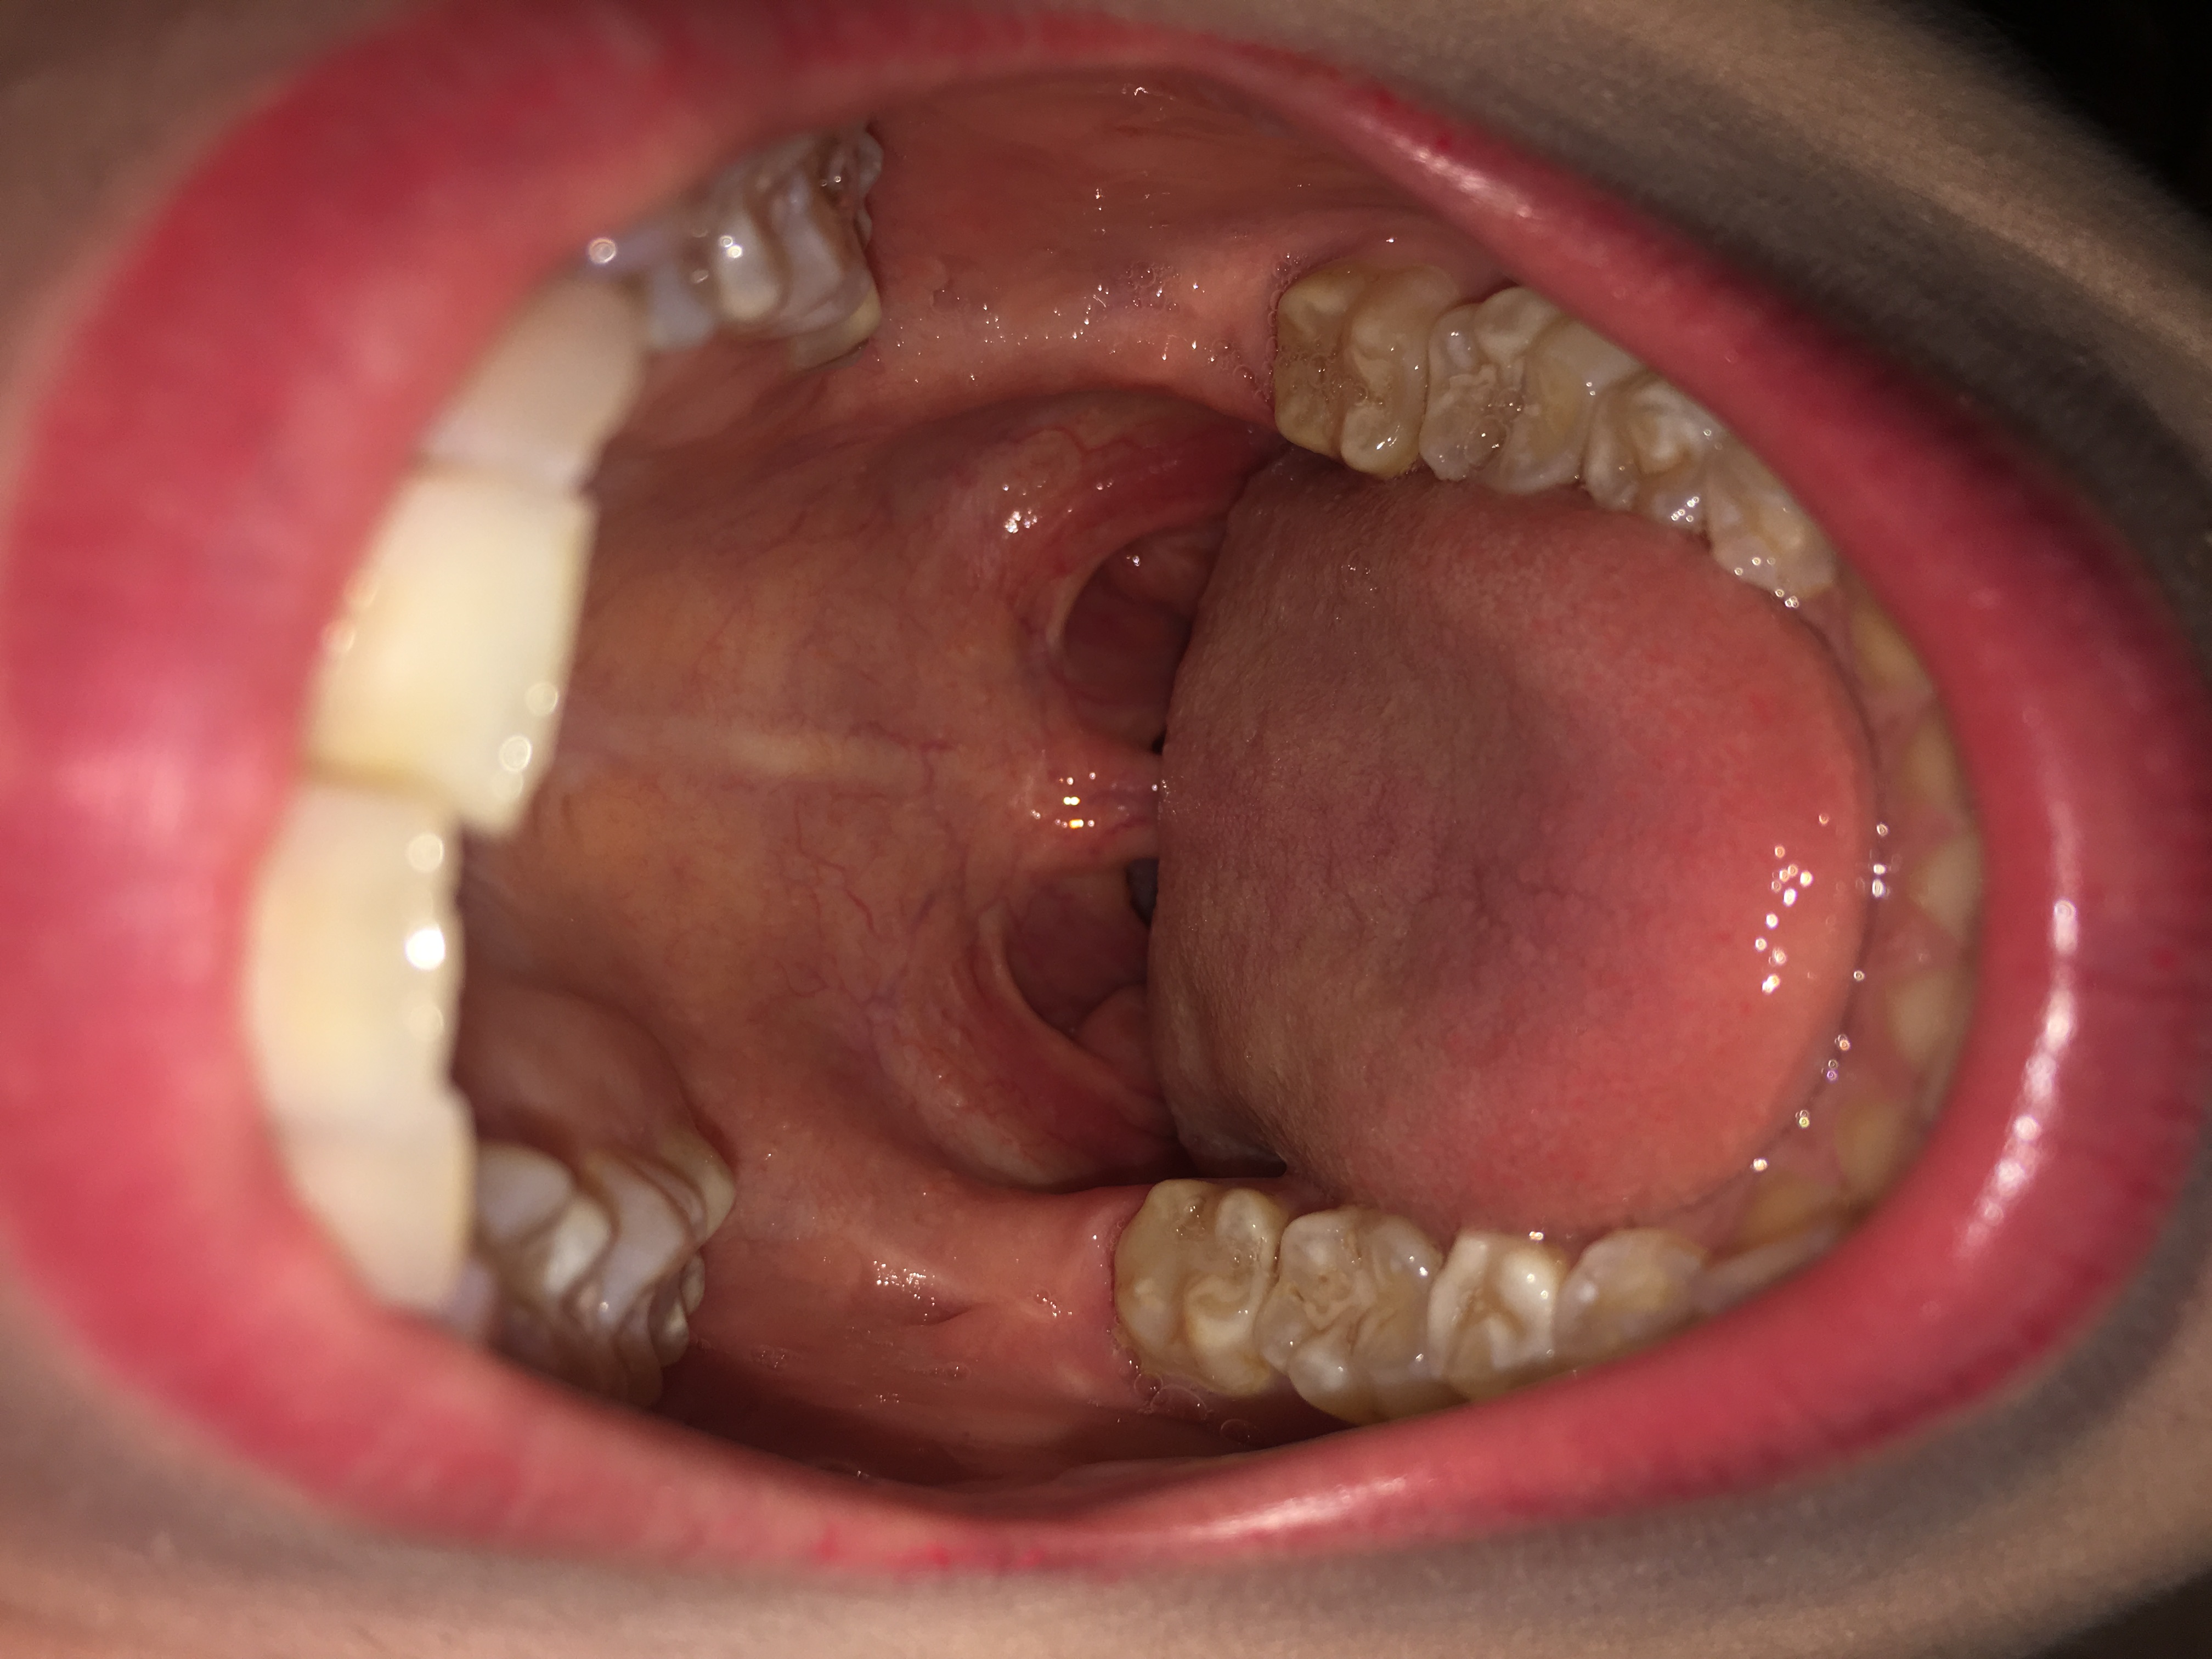

Vor allem durch Husten, Niesen, Naseputzen und Sprechen steigt die Ansteckungsgefahr.Sie kühlen die gereizte Schleimhaut im Mund und Rachen. Bei einer Rachenentzündung (Pharyngitis) ist die Schleimhaut im Rachen entzündet. Der Schmerz wird manchmal auch in den Ohren gespürt.Eine Schleimhautentzündung (Mucositis) kann im Mund-Rachenraum, im Magen-Darm-Bereich und in den Harnwegen vorkommen. Zudem ist der Halsraum gerötet und geschwollen.Belag im Rachen ist nichts Gefährliches, kann aber Beschwerden verursachen, vor allem wenn er zusammen mit Fieber oder Halsschmerzen auftritt. Halsschmerzen sind ebenfalls ein mögliches Symptom von Stillem Reflux. Hausmittel haben ihre Grenzen. Im Folgenden klären wir . Auslöser einer Rachenentzündung sind meistens .Tabakrauch enthält eine komplexe .Sowohl die Reizungen im Hals und die vermehrte Schleimbildung als auch der Hang der Stimme zur Heiserkeit können dazu führen, sich ungewöhnlich oft räuspern zu müssen. Thomas Meier-Lenschow. Wenn die typischen Symptome der Speiseröhrenentzündung wie Kloß im Hals, Sodbrennen, saures Aufstoßen, Schluckbeschwerden und/oder Brennen und Schmerzen im Oberbauch länger als zwei Wochen anhalten, sollten Betroffene ärztlichen Rat suchen. Seltener verursachen Coxsackie-, Herpes-simplex-, oder Echoviren den entzündeten Rachen. Rachenentzündungen werden in der Regel durch . Die Kehlkopfentzündung heilt normalweise von alleine aus. brennendes, kratziges Gefühl. Viel Schlaf und Ruhe sowie . Schmerzen und Brennen in der Magengegend. Bei infektiösem Husten, egal ob produktiv oder unproduktiv, helfen zum Beispiel Codeine. Infektionen des Rachens und/oder der Mandeln kommen vor allem bei Kindern häufig vor.Granit Xhaka sieht gegen den BVB seine fünfte Gelbe Karte. Ansteckung & Übertragung.

Nur selten führen Bakterien zu solchen Symptomen.Die Symptome einer Pharyngitis sind ein geröteter Rachen und Gaumen; auch die Halslymphknoten sind häufig gerötet und geschwollen. Rachenentzündung – . Weißer Belag auf den Mandeln ist ein Anzeigen dafür, dass sich Eiter gebildet hat. Häufiges Aufstoßen von Luft oder Mageninhalt. durch Sprechen, Niesen und Husten übertragen.

Suchen Sie außerdem einen Arzt auf, wenn Blutungen im Rachenraum mit einem der folgenden Symptome einhergehen. Zunächst kann der Hals aus verschiedenen Gründen gereizt sein, sei es durch E-Zigaretten, herkömmliche Zigaretten oder sogar CBD Grass, das oft schwerer für die Atemwege ist als andere Produkte. Bei trockenem Husten (Reizhusten) hilft es zuerst mal, viel zu trinken – entweder Wasser oder Tee. Gegen die Entzündung hilft Speiseeis allerdings nicht. Dazu gehören Zahnpasta, Alkohol, Hamamelis . Die Halsentzündung kann sowohl mit Hausmitteln als auch mit .Wie bereits erwähnt Komma ist eine Pharyngitis oftmals eine Folge von gereizten oder beanspruchten Schleimhäuten. Lesen Sie hier, welche .Die Rachenentzündung zählt zu den häufigsten Krankheitsbildern in der Hausarztpraxis und betrifft insbesondere in der kalten Jahreszeit viele Menschen.Stiller Reflux: Magensaft im Rachen. Auftreten können zudem Schluckbeschwerden, . In der Folge entwickeln sich Halsschmerzen, die manchmal bis in die Ohren ausstrahlen, und . Sie wird durch Infekte hervorgerufen .Letzte Aktualisierung: 13.Die nicht-bakterielle Rachenentzündung entsteht beispielsweise durch Erkältung und somit durch Viren. Einteilung & Formen.

Erstes Anzeichen einer Rachenentzündung ist oft das typische „Kratzen im Hals. Die üblichen Erkältungssymptome sind Husten, Schnupfen, erhöhte Temperatur bis leichtes Fieber (37,5-38,5°C), allgemeine Abgeschlagenheit und natürlich Halsschmerzen. Zu den typischen Beschwerden gehören Sodbrennen, Luftaufstoßen, Schluckbeschwerden, Heiserkeit und Kloßgefühl im Hals, mitunter auch . Die Mandeln sind rot und geschwollen und haben manchmal .Liegt eine Speiseröhrenentzündung vor, sind zusätzlich folgende Symptome möglich: Schmerzen und Brennen in der Speiseröhre. Mit Kräutertee gegen Halsentzündungen. ©RFBSIP – Fotolia. Salz hat antiseptische und antimikrobielle Eigenschaften, die helfen, jede mikrobielle Infektion zu beseitigen, indem sie das Wachstum einschränken.Bei der Behandlung geht es .Reinigen Sie Ihre Zahnzwischenräume mit Zahnseide oder Mundduschen, wie der Waterpik WP 660 oder der Philips Sonicare AirFloss.Saurer Mageninhalt fließt dabei – vor allem nachts – aus dem Verdauungstrakt nach oben in die Speiseröhre. Pharyngitis) handelt es sich um eine lang anhaltende oder dauerhafte Entzündung der Rachenschleimhaut. Wird die Kehlkopfschleimhaut durch Säure gereizt, kann es zu einer Kehlkopfentzündung kommen (Laryngitis).Symptome einer Racheninfektion.Rachenentzündung – was kann man selbst tun? Eine akute Rachenentzündung tritt am häufigsten im Herbst und Winter, also während der klassischen Erkältungszeit auf. Sie ist eine der häufigsten Erkrankungen im Hals-Nasen-Ohren-Bereich. Damit sind alle Krebsarten gemeint, die in diesem Körperbereich auftreten.

Aber man kann seinem Körper dabei helfen, indem man viel trinkt und sich moderat bewegt.Rachenentzündung – Definition und Häufigkeit.Vorwiegend startet der entzündliche Prozess mit einem Kratzen im Hals, welches auf eine virale oder bakterielle Infektion zurückzuführen ist, gefolgt von weiteren typischen Symptomen wie Husten, Schnupfen und/oder Fieber. Sind die Mandeln mit . ständiges Räuspern. Doch das Immunsystem von Betroffenen identifiziert den Blütenstaub fälschlicherweise als Gefahr und setzt eine Abwehrreaktion . Einige Betroffene haben Fieber, Kopfschmerzen und eine Magenverstimmung.Entzündungen in Mund und Rachen treten meist in Form von Schwellungen und Rötungen auf, die äußerst schmerzhaft sein können. Von einer Rachenentzündung betroffene Menschen haben normalerweise starke Schmerzen beim Schlucken und Sprechen.